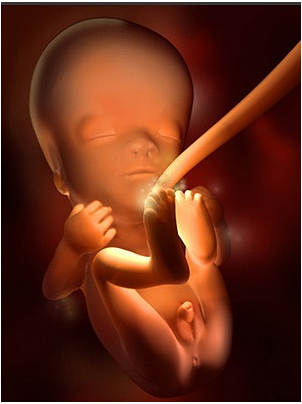

怀孕第28周胎儿图 从现在开始,你就进入了孕晚期,要注意的事情很多呦!你要每天做胎动...

怀孕第28周胎儿图 从现在开始,你就进入了孕晚期,要注意的事情很多呦!你要每天做胎动... -

怀孕第34周此时胎儿已经为分娩做好了准备,将身体转为头朝下的姿势。你最近会感觉有一点儿累,这...

怀孕第34周此时胎儿已经为分娩做好了准备,将身体转为头朝下的姿势。你最近会感觉有一点儿累,这... -

怀孕第38周恭喜准妈妈,从现开始你的宝宝已经是足月儿了,随时可能出来和你见面哦!你现在是不是...

怀孕第38周恭喜准妈妈,从现开始你的宝宝已经是足月儿了,随时可能出来和你见面哦!你现在是不是... -

怀孕第39周你的小宝宝现在已经准备好向这个世界报到了,准备好了吗,年轻的爸爸妈妈?也许明天?...

怀孕第39周你的小宝宝现在已经准备好向这个世界报到了,准备好了吗,年轻的爸爸妈妈?也许明天?... -